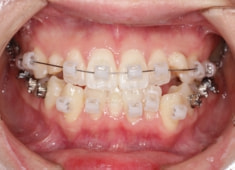

先天欠如歯両側上顎3番

治療法:フルパッシブブラケット:T21

治療中